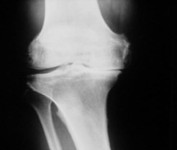

Arthrose ist eine durch Verschleiß bedingte Erkrankung des Gelenkknorpels, der das altersübliche Ausmaß übersteigt. Die Ursachen hierfür sind vielfältig (Genetik, Überlastung, Alter, Gewicht, Sport) und geht in der Regel mit einer schmerzhaften Entzündung der Gelenkschleimhaut einher (Arthritis).

Bei fehlgeschlagenen konservativen Therapiemaßnahmen und anhaltenden Beschwerden sind wahlweise auch operative Therapiemaßnahmen zu erwägen. Abhängig vom Alter des Patienten und vom Ausmaß des Knorpelschadens werden verschiedene operative Therapien angeboten.